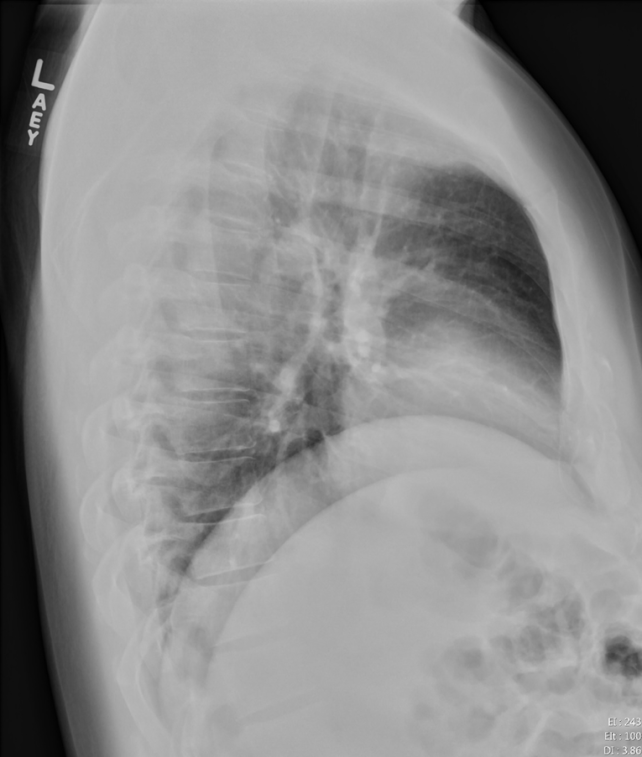

Sometimes it is not obvious on the PA view which side a consolidation is on because it may be located in the posterior sulcus and therefore obscured.

We can use the lateral view and an understanding of the silhouette sign to help determine when a consolidation is present and which side it is on.

![]() | ![]() |

“Normal” View of PA and Lateral Chest

Notice how on this normal lateral the diaphragms extend all the way from anterior to posterior. The right diaphragm usually is slightly higher than the left and the left often will not extend fully anterior because of the heart being adjacent to it.

Now notice how the left diaphragm silhouette no longer extends posteriorly all the way. This is because it has lost its silhouette because there is a dense consolidation directly adjacent to it.

Loss of Left Diaphragm Due to Consolidation